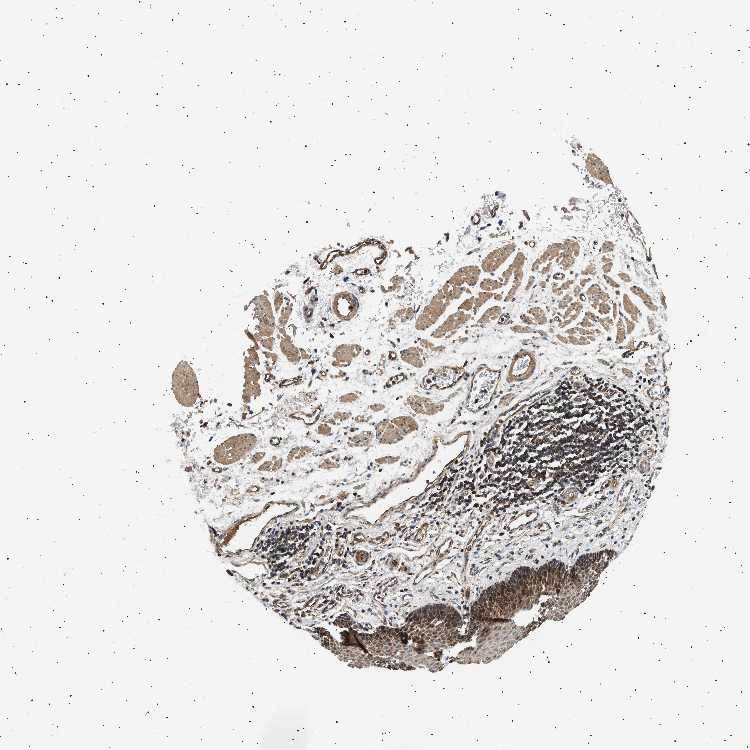

ESOPHAGUS - Antibody stainingi

Antibody staining in the annotated cell types in the current human tissue is reported as not detected, low, medium, or high, based on conventional immunohistochemistry profiling in selected tissues. This score is based on the combination of the staining intensity and fraction of stained cells.

Each image is clickable and will lead to virtual microscopy that enables deeper exploration of all samples and also displays staining intensity scores, fraction scores and subcellular localization as well as patient and tissue information for each sample.

Antibody HPA021293Antibody HPA021300Antibody HPA021337

Squamous epithelial cells HighMediumMedium